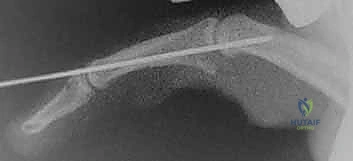

2. التصوير الشعاعي (X-Rays)

الأشعة السينية هي الأداة الذهبية لتشخيص كسور وخلع مفصل PIP. يطلب الدكتور هطيف صوراً في ثلاثة أوضاع:

* الوضع الأمامي الخلفي (AP): لتقييم محاذاة المفصل والبحث عن أي انحراف جانبي.

* الوضع الجانبي الحقيقي (True Lateral): وهو الأهم على الإطلاق. من خلاله يتم تقييم حجم القطعة العظمية المكسورة، ودرجة الانزلاق الظهري (Subluxation). يبحث الدكتور هطيف عن "علامة V" (V-sign) التي تشير إلى عدم تطابق الأسطح المفصلية.

* الوضع المائل (Oblique): لرؤية تفاصيل الكسر من زوايا مختلفة.

الخطوة 6: التثبيت المؤقت (اختياري)

في بعض الأحيان، ولضمان التئام الصفيحة في مكانها الجديد دون إجهاد، قد يقوم الدكتور هطيف بتمرير مسمار معدني رفيع (K-wire) عبر المفصل لتثبيته في وضعية ثني خفيفة (حوالي 20 إلى 30 درجة) لمدة أسبوعين إلى ثلاثة أسابيع.